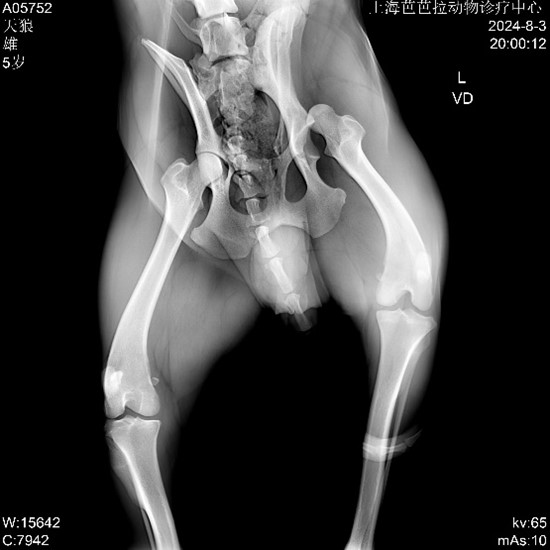

▼ Pre-op Imaging

▲ Diagnosis: Left femoral head luxation